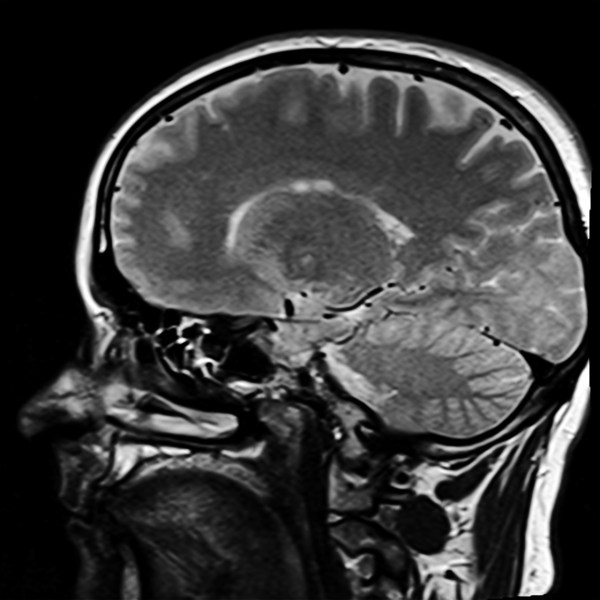

Read this article, “An introduction to diffusion tensor image analysis”, to get an idea of just what “diffusion tensor imaging” is, but be prepared for abstruseness. Yesterday I posted about the brain effects of COVID-19, and a paper came up that talked about changes on DTI. Unfortunately, the changes are ill-defined and the field of DTI is new and not well established.

I cited this article but reading it didn’t really clarify just what DTI is– it only made it clear that the changes one finds don’t correspond to clear pathological changes in the brain. The technique works well in squid axons, but that’s not what we’re interested in right now.